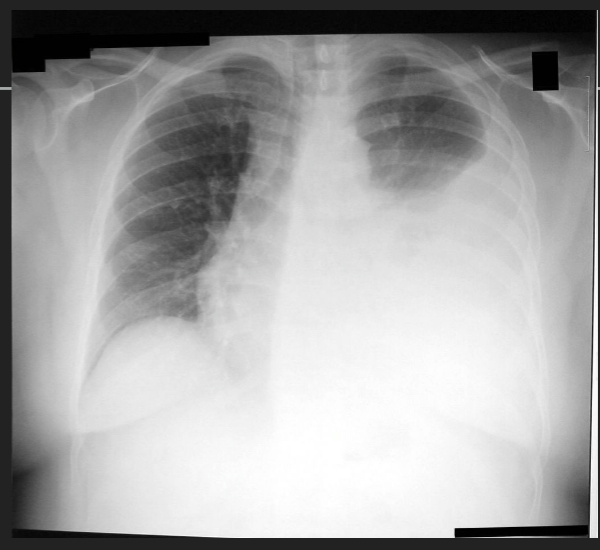

Q

A

tension pneumothorax